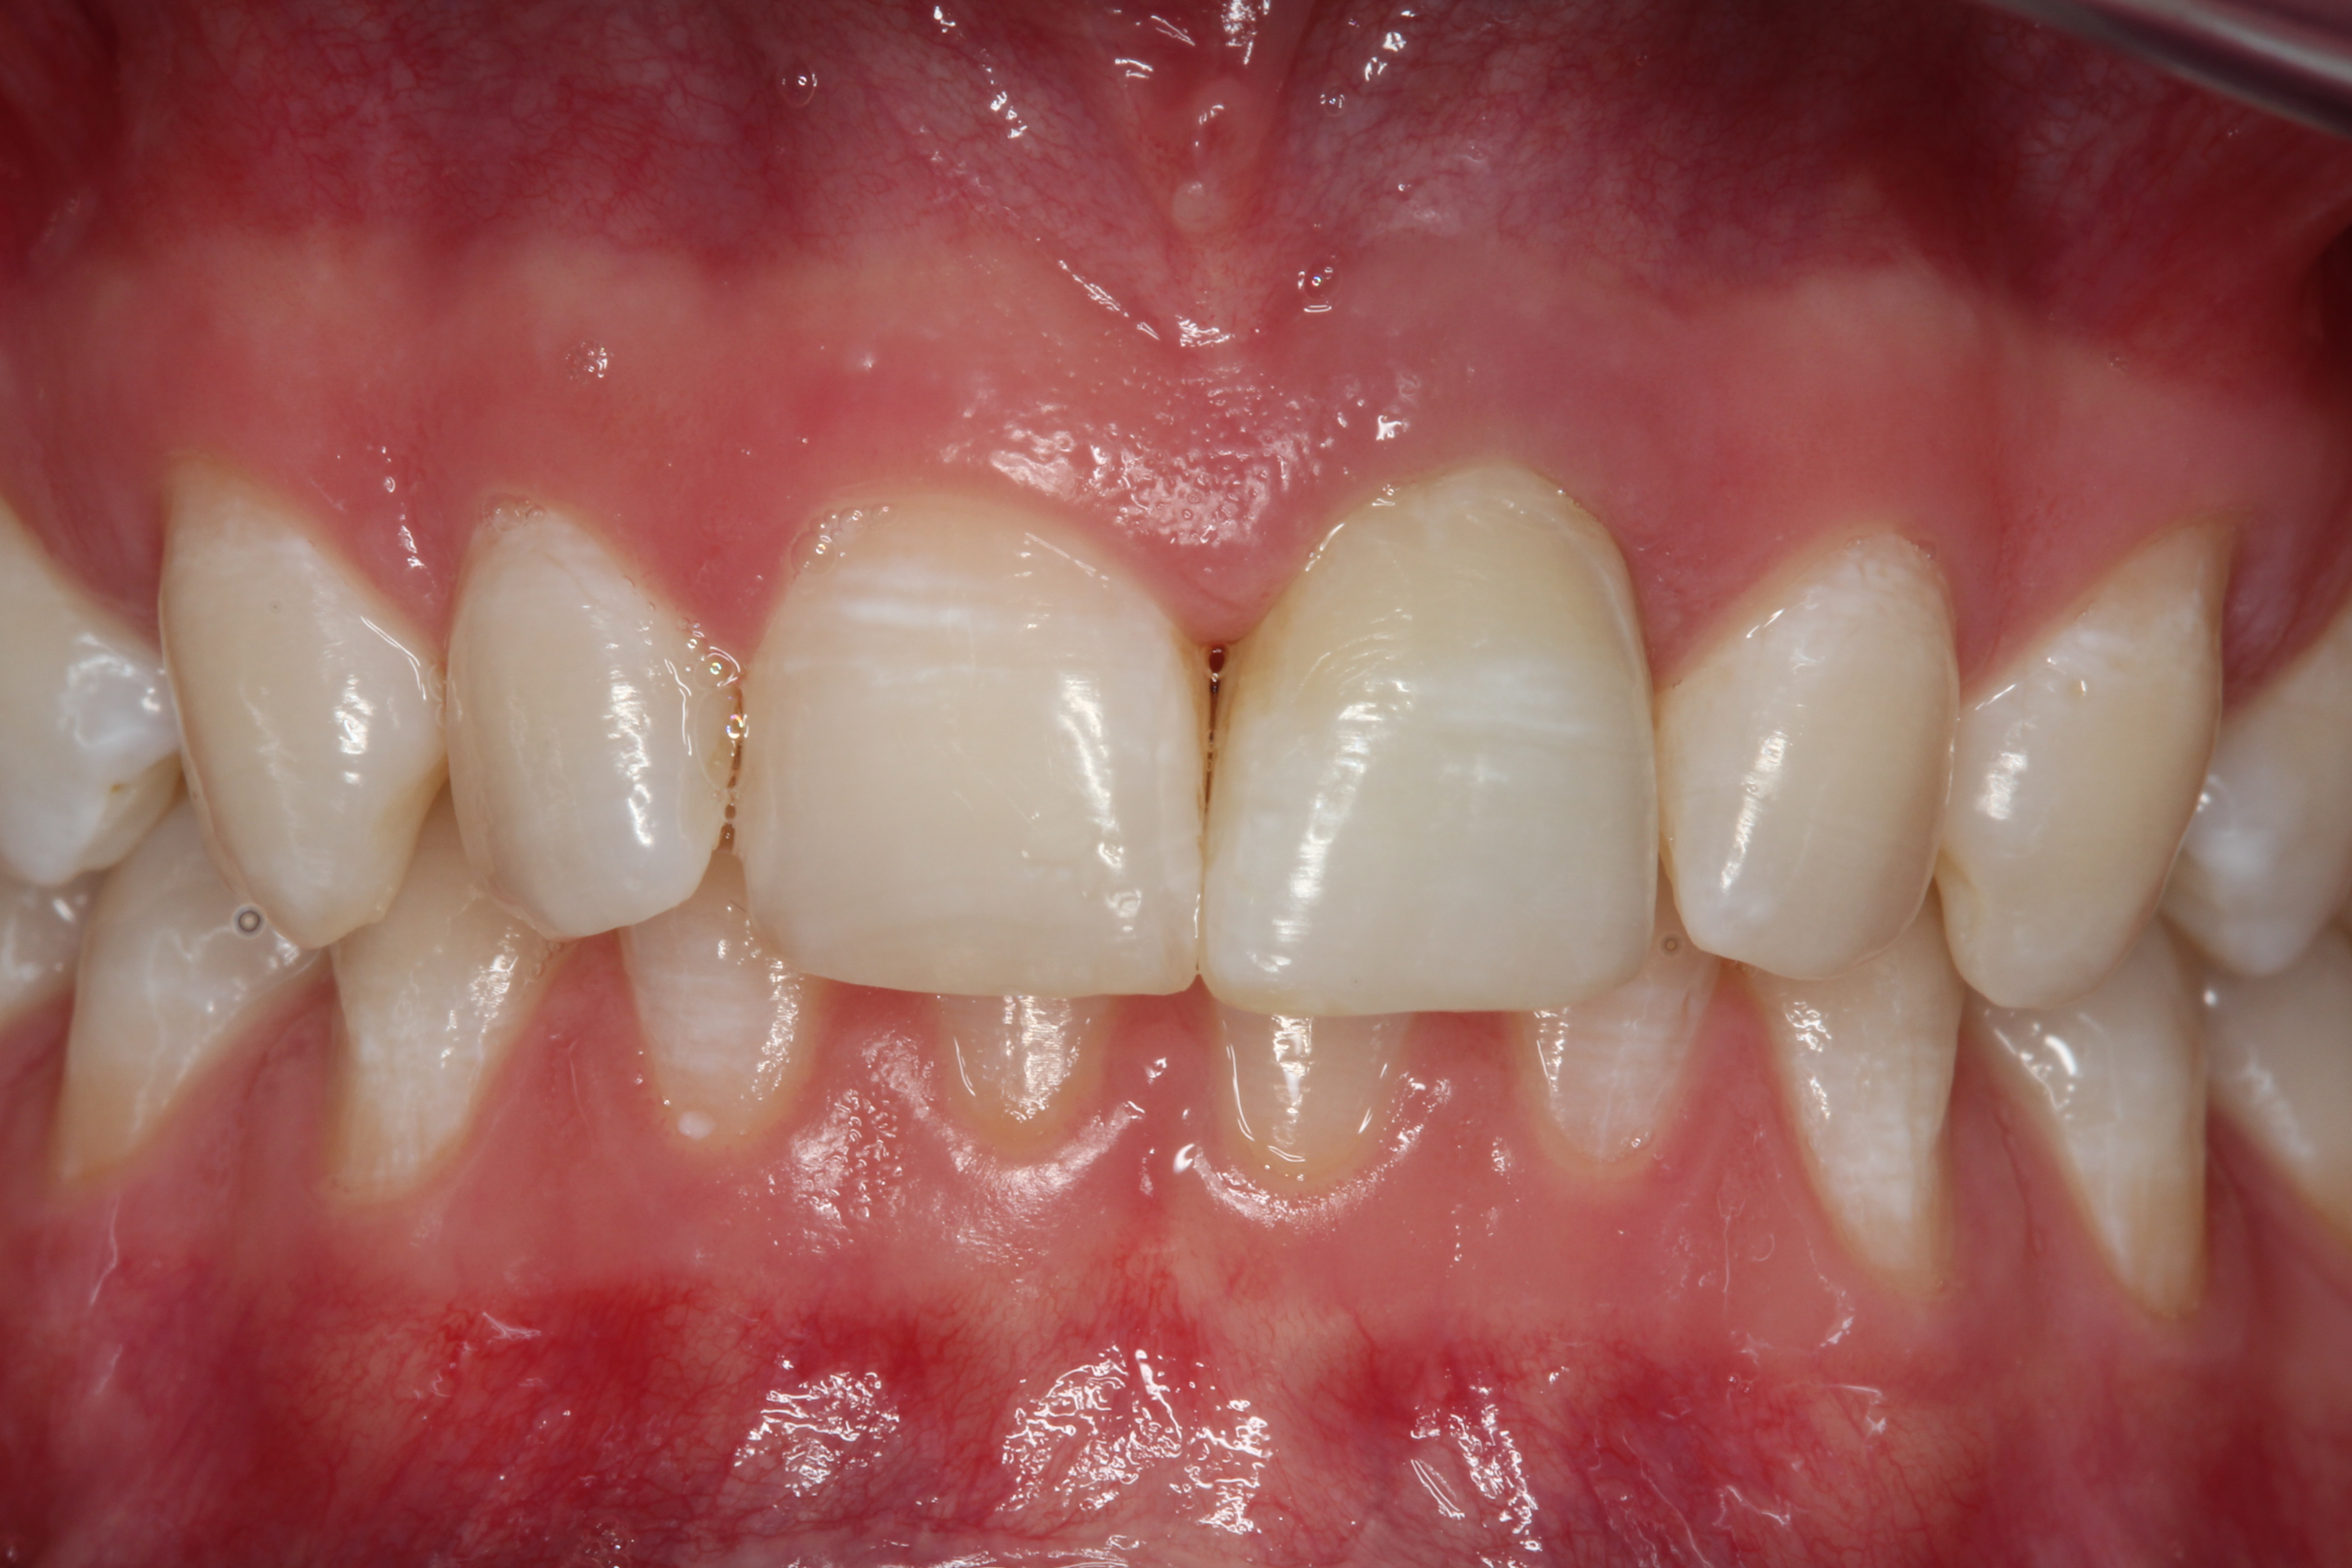

Fig 3. Retracted photograph, teeth apart.

Figure 3

A young man presented with a fractured maxillary left-central incisor on a Monday morning after a Saturday evening discussion that did not end well (Figure 1). Visual oral examination and palpation of the structures revealed mobility of 3+, pain on palpation and percussion, a thick soft-tissue profile, and a low lip line. Gingival zeniths were irregular, there was a class II division 2 deep bite, and the periodontium was healthy overall (Figure 2 through Figure 4). Radiographs requested at the time of the initial visit were periapicals, panoramic, and CBCT images (Figure 5 and Figure 6). After all images and information were reviewed and the extent of his injury was discussed, the patient was presented with the following options: removable prosthetics, fixed partial denture, extract and do nothing, or extract and place a dental implant with bone augmentation.